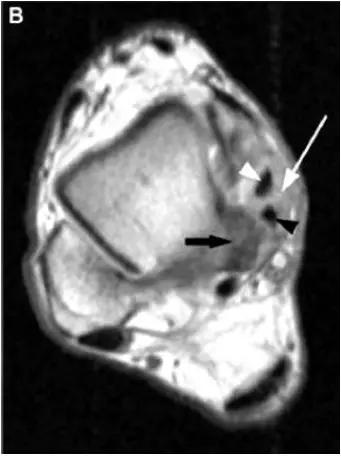

轴位示意图示后内侧撞击综合征:M:内踝;L:外踝;TP:胫后肌腱;FDL:趾长屈肌腱;Talus:距骨。短箭:距骨胫骨间肌腱深层纤维;箭头:距骨胫骨间肌腱后部纤维。

X线平片示胫骨后部骨赘形成,MR质子像黑箭示胫骨内后侧骨赘形成,白箭示内后侧软组织增厚, 白箭头:胫后肌腱;黑箭头:趾长屈肌腱